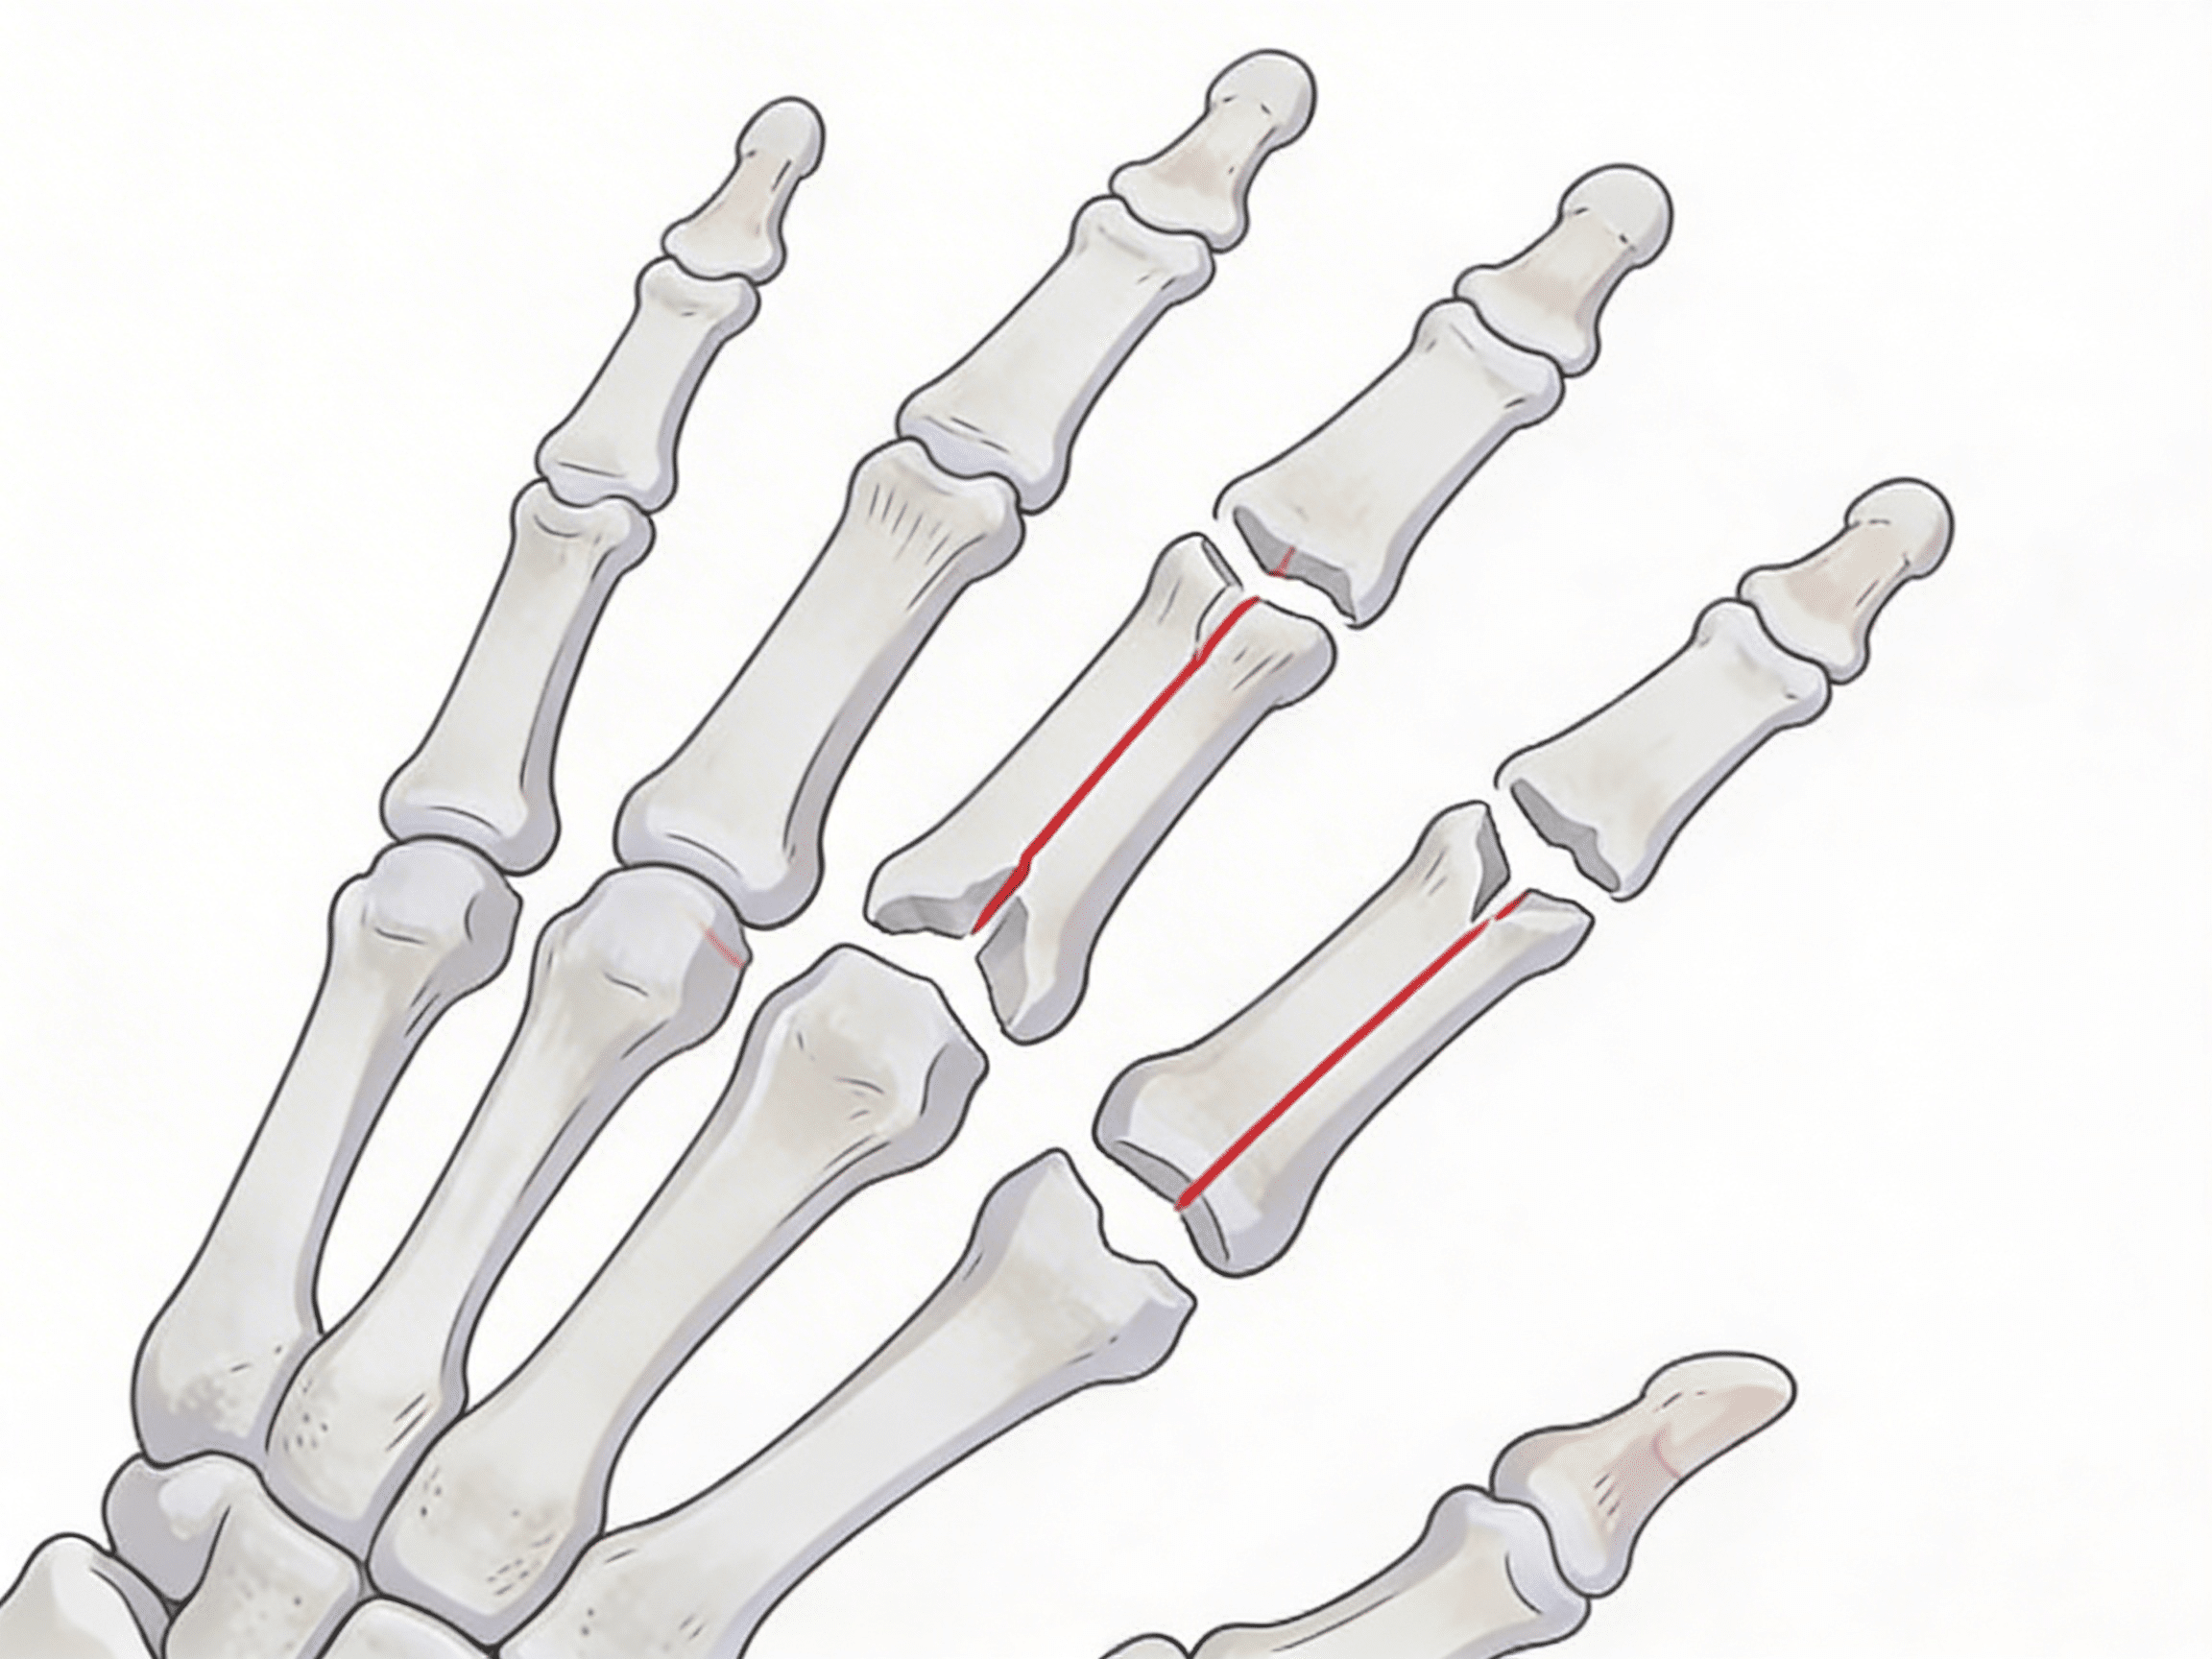

According to the American Society for Surgery of the Hand, approximately 1.5 million hand fractures occur annually in the United States, with distal radius fractures (wrist) comprising 25%, metacarpal fractures (hand) 40%, and phalangeal fractures (fingers) 35%[5]. The critical difference between optimal healing and permanent stiffness often comes down to seeking appropriate wrist, hand, and finger fractures care within the first 2-3 hours of injury. Our orthopedic emergency capabilities include immediate buddy taping, ulnar gutter splinting, thumb spica application, and sugar tong splinting techniques preventing displacement while awaiting definitive treatment.

Source: CDC Hospital Emergency Outcomes Study 2024

Research from the Journal of Hand Surgery demonstrates that delayed scaphoid fracture treatment increases avascular necrosis rates by 45% when immobilization exceeds 24 hours[6]. This timeline becomes even more critical for displaced finger fractures, where rotational deformity develops within 4-6 hours of injury, requiring immediate reduction preventing permanent grip weakness and overlap deformity[7]. Our hand surgery emergency capabilities include immediate digital nerve blocks, hematoma blocks for fracture reduction, and emergency consultation when open fractures or complex intra-articular injuries require operative fixation.